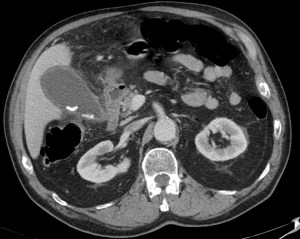

Veamos también un caso de coledocolitiasis diagnosticado por TC abdominal.